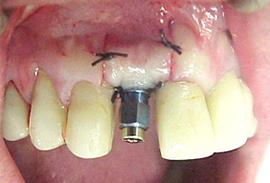

Figura n°8. A fotografia não esta permitindo ver os detalhes, mas a cavidade final está pronta, para receber o implante Conect de Ø4,3 X 10,0mm

Figura n°9. Este é o implante Conect colocado, acreditamos que ele tenha ficado em uma posição ideal. O montador do implante serviu de posicionador para o similar ser vazado em gesso. Isto é, usou-se o guia cirúrgico para fixar o montador do implante, que foi levado ao modelo de estudo e fixado o similar.

Figura n°10. Resultado final da técnica cirúrgica, onde se procurou colocar a gengiva do retalho em uma posição bem cervical para dar estética na coroa. A partir deste momento iniciaram-se os procedimentos protéticos. Há que se tomar muito cuidado nestes procedimentos com a biossegurança, pois o campo cirúrgico está aberto o que teoricamente poderia facilitar uma contaminação e comprometimento dos procedimentos realizados.

Figura n° 11 A e B.

A) Vista oclusal do modelo de trabalho, com guia cirúrgico em posição, confeccionado em resina acrílica ativada quimicamente pela (R.A.A.Q) e dente de estoque, mostrando perfuração para posicionar a broca inicial. B) Vista vestibular mostrando a posição planejada para a coroa estética, observa a relação cervical do dente de estoque, com o orifício onde estava a raiz do 12 no guia cirúrgico.

Figura n°12. Implante em posição, retalho posicionado; o monta implante preso ao guia cirúrgico, será utilizado para fazer a transferência da posição da fixação para o modelo de trabalho.